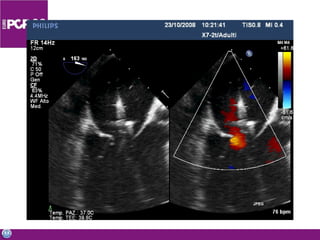

Imaging and other enabling technologies ICE 3D echo Multislice CT MRI Stereotaxis Combinations

Transeptal puncture “The” endovascular skill for mitral valve Difficult and risky Echo guidance Safety Precision A surgeon invented it – so we can learn it Few (<5%) interventional cardiology centers routinely perform this technique

Imaging and otherenabling technologies ICE 3D echo Multislice CT MRI Stereotaxis Combinations

• #53 Not only transeptal puncture can be facilitated by echo, but generally speaking….. Imaging is the most important enanbling technoilogy for PVI and surgeons involved in the field should be exposed to most of these technolgies